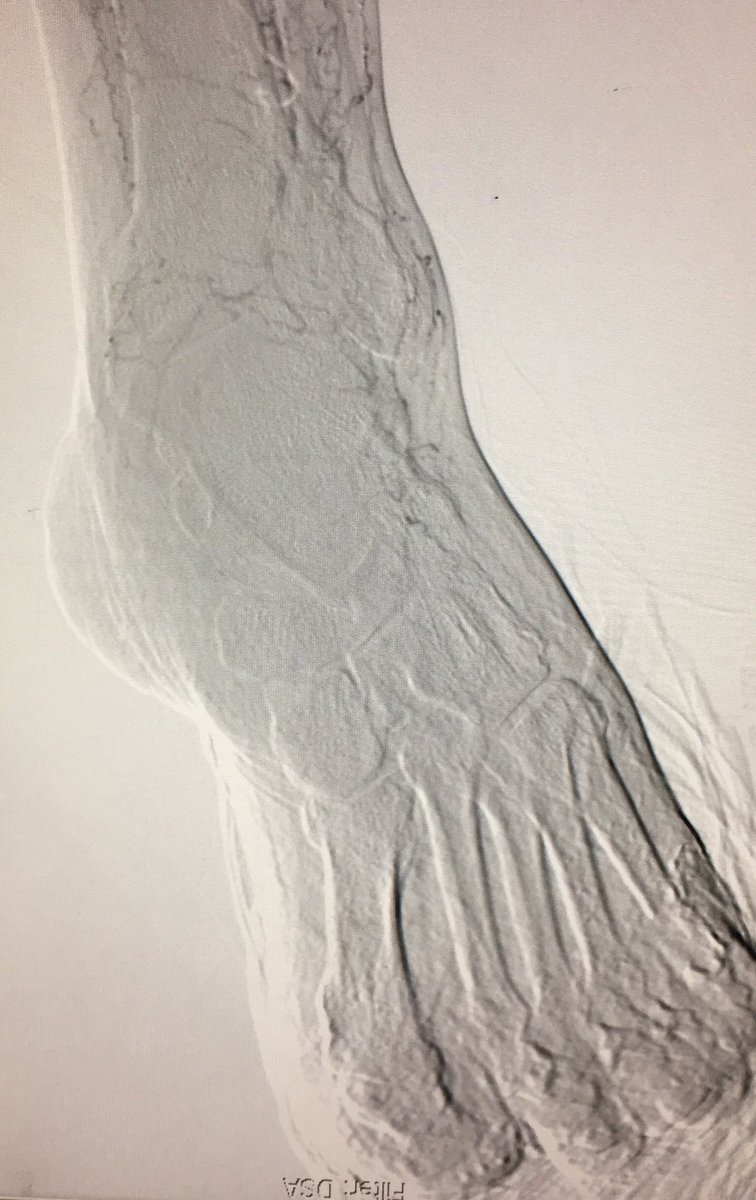

An image is worth a 1,000 words - what does this one depict ? Participate in quiz here🔗pcronline.com/Cases-resource…

🖼️submitted by Eirini Dri, Sofia Vaina, Anastasios Milkas, Konstantinos Tsioufis from 🇬🇷 and selected for #EuroPCR

#interventionalcardiology #cardiotwitter